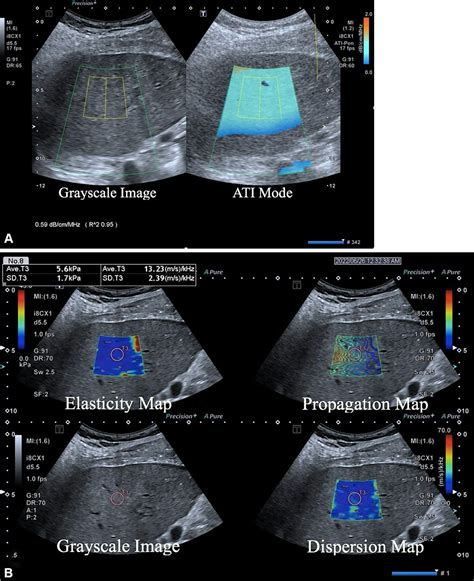

Advanced imaging techniques, such as contrast-enhanced ultrasound or subsequent MRI/CT scans, may be requested if the initial findings are inconclusive. These follow-up tests provide higher resolution and dynamic blood flow data, allowing medical professionals to differentiate between benign and malignant liver processes with greater precision.

For patients with chronic liver conditions, such as Hepatitis B or C, serial imaging is essential. By comparing current liver ultrasound images with previous scans, doctors can monitor the progression of disease or the success of ongoing treatments. This longitudinal approach is vital for the early detection of hepatocellular carcinoma, which is significantly easier to treat when found during the early stages of development.

Furthermore, ultrasound has become a standard tool for evaluating the efficacy of lifestyle changes in patients with Non-Alcoholic Fatty Liver Disease (NAFLD). As patients lose weight or modify their diets, sonographic follow-ups can visually document the reduction of fat accumulation within the liver cells, serving as a powerful motivational tool for the patient and a tangible metric for the physician.